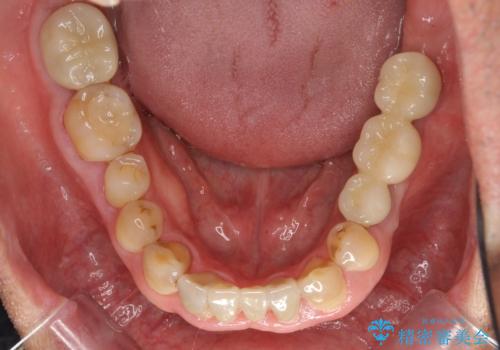

奥歯のインプラント 大人になって残っていた乳歯がダメになった

- 奥歯のブリッジの違和感を主訴に来院。

乳歯を使ってブリッジにしていましたが、支台歯が両方虫歯になっており、根が短くなって持たなくなった乳歯を抜いて、インプラントにすることになりました。